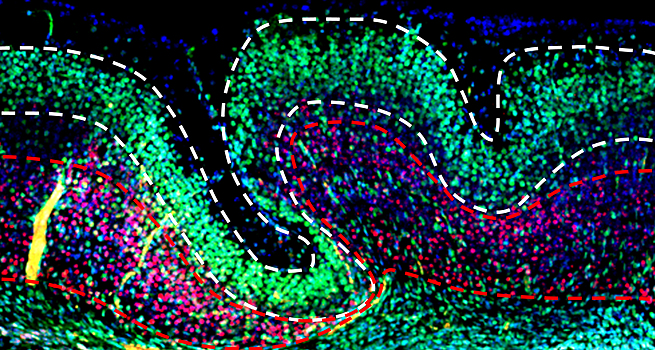

В начале этого месяца, на ежегодной конференции нейробиологического общества, две группы ученых продемонстрировали новые технологии, которые могли бы подарить нам вечное блаженство. Что, если секрет вечного счастья заключается в мозговом имплантате? Только представьте: набор крошечных электродов тихо сидит в разных частях мозга, регистрируя электрическую активность этого органа в реальном времени. Данные передаются персональному алгоритму — «карте настроения» — который может оценивать общее настроение человека, основываясь на одних только мозговых волнах. Когда система регистрирует паттерны, указывающие на начало эпизода депрессии, она посылает электрические сигналы в центр настроения мозга. Под бдительным оком алгоритма система продолжает стимуляцию до тех пор, пока неисправные цепи не будут возвращены в свое «счастливое» состояние. Алгоритм полностью самостоятельный. Каждый сигнал, каждая настройка прячутся под крышечкой. Системе не нужно руководство врача, и человек не знает о сигналах — лишь чувствует общее облегчение грусти. Финансируемые агентством DARPA ученые надеются, что эти футуристические имплантаты «замкнутой петли» однажды помогут ветеранам с ПТСР — посттравматическим стрессовым расстройством — или людям с сильной депрессий, которая не поддается медикаментозному лечению. «Мозг сильно отличается от всех остальных органов из-за своей сетевой работы и способности к адаптации», говорит Джастин Санчез, менеджер программы в DARPA. «Замкнутые нейронные интерфейсы в реальном времени позволяют нам отойти от традиционного статического взгляда на мозг и перейти к точному лечению». Хотя эта система в первую очередь создавалась для помощи людям с психическими заболеваниями, ее потенциальное влияние может выходить далеко за пределы этого. Очевидно, хирургия на головном мозге — высокая цена за «стимулированное счастье», особенно для обычного человека. Тем не менее вполне возможно, что компоненты системы в конечном итоге могут быть заменены неинвазивными способами измерения и стимулирования деятельности мозга. Что тогда произойдет? Сможете ли вы доверить другим прямой, постоянный, хронический доступ к вашим внутренним чувствам? Возникнет ли у вас соблазн утопить все эмоции в счастье? Копайте глубже Конечно, все это возможно лишь при условии, что система работает. В основе системы лежит старая технология глубокой стимуляции мозга (ГСМ). Одобренная впервые для лечения двигательных симптомов во время болезни Паркинсона, ГСМ полагается на электроды, непосредственно имплантированные в мозг для доставки электрических импульсов. Эти импульсы взаимодействуют с локальными нейронами и меняют их активность. Подобно тому, как бросать камешек в пруд с неподвижной водой, изменения в этой основной группе нейронов пульсируют по нервным цепям. Хотя нейробиологи не совсем поняли конкретные механизмы, ГСМ, похоже, облегчает множество неврологических расстройств. По крайней мере так показали некоторые рассеянные испытания. В ходе одной из первых демонстраций силы ГСМ ученые включали и выключали систему стимуляции, спрашивая пациента с депрессией о его самочувствии. Невероятно, но пациент сообщал только о «приподнятом настроении», когда система работала — даже осознавая, что ученые активировали электрические импульсы. Эта и другие ранние истории успеха привели к недавнему крупномасштабному клиническому испытанию с участием 90 человек с депрессией. Плохая новость: в среднем исследования не обнаружили никаких улучшений после года лечения. Но доктор Эдвард Чанг, нейробиолог из Калифорнийского университета в Сан-Франциско, который руководит одним из проектов, считает, что это только начало. Большинство систем ГСМ лечат депрессию одинаково, несмотря на то что люди по-разному ее переживают. Эти системы окунают мозг в постоянные электрические импульсы. Протокол стимуляции задается врачом, а не актуальным состоянием мозга пациента. По мнению Чанга, важно создать имплантаты, специально разработанные для индивидуального лечения каждого — и включать систему только в случае необходимости. Карта настроения Пригласив доктора Омида Г. Сани, инженера-электротехника из Университета Южной Калифорнии, ученые разработали алгоритм, который переводит волны мозга в субъективные чувства настроения. Команда работала с шестью пациентами с эпилепсией с уже имплантированными электродами, чтобы отследить источник их приступов. На протяжении трех недель активность мозга пациента тщательно отслеживалась, в то время как настроение мониторилось по стандартному опроснику. Сравнивая эти два типа информации, ученые разработали алгоритм, который извлек небольшое количество «нейронных предикторов» — динамических паттернов активности нейронных сетей — которые могли точно предсказывать постоянно меняющиеся чувства человека. Возникло несколько «очагов», включая лимбическую систему, ранее идентифицированный центр по управлению настроением и мотивацией. «Эти биомаркеры динамического настроения и алгоритмы, расшифровывающие настроение, могут представить картину процессов мозга, которые лежат в основе управления настроением», пришел к выводу Сани. Это также первый шаг в направлении персонализированных методов стимулирования мозга для лечения депрессии. Как пишет Nature, Сани и Ченг уже разработали тестовую систему, готовую к проведению испытаний на людях. Подобные замкнутые системы уже были протестированы на нескольких людях, но Ченг подчеркивает, что эти предварительные результаты должны быть проверены дополнительно. Пересечь черту Вторая команда ученых под руководством нейрохирурга Эмада Эскандара из Массачусетского госпиталя предприняла несколько иной подход. Подход так называемой трансдиагностики рассматривает общие черты различных психических расстройств, а не конкретное расстройство настроения. Поэтому ученые разработали алгоритмы, которые захватывают и выделяют активность мозга, ассоциируемую с общеизвестными аспектами плохого настроения — например, повышенное беспокойство, забывчивость и недостаток эмпатии. Эскандар считает, что волны мозга — это лишь малая часть данных. Его команда также надеется записать активность отдельных нейронов, чтобы идентифицировать те, которые приводят к психическим заболеваниям. Цель, конечно, крайне амбициозная. В случае успеха Эскандар сможет отслеживать симптомы болезни, начиная одиночными нейронами и заканчивая нейронными схемами активности мозга — и тогда появится возможность составить многослойный атлас для врачей, которые смогут по нему находить лучшие методы лечения. Изучая собственные возможности, ученые представили на конференции алгоритм, который определяет, когда люди упускают что-то из виду из-за дефицита внимания. Участников попросили сосредоточиться на задаче — например, определять эмоции на генерируемых компьютером лицах — параллельно отслеживая активность их мозгов. Алгоритм в итоге научился выявлять паттерны нейронной активности, связанной с отвлечением. Когда ученые стимулировали мозги добровольцев в регионе, отвечающем за принятие решений, их эффективность решения задач заметно улучшилась. Также исчезли структуры нейронной активности «рассеянного мозга». В настоящее время команда работает над автоматизацией процесса, чтобы алгоритм непосредственно вызывал стимуляцию во время дефицита внимания. Мозг наизнанку Если эти проекты DARPA будут реализованы, наши методы лечения психических заболеваний радикально изменятся. Но ученые переживают, что мы можем вступить на минное поле этики. Чтобы полностью реализовать эти замкнутые системы, алгоритм должен всегда знать истинные чувства человека. Хотя он не сообщает о колебаниях настроения, эти данные доступны исследователям и врачам. И если такое лечение когда-либо будет коммерциализовано, смогут ли пациенты доверять компаниям сохранение своих чувств и эмоций в безопасности и неприкосновенности? Некоторые ученые также беспокоятся о том, что таблетка электрического счастья изменит эго человека. «При любом лечении заболеваний мозга мы рискуем сделать всех одинаковыми, лечить любое отклонение от нормы как болезнь», считает доктор Карен Роммельфангер из Университета Эмори, рассуждая на тему ГСМ. «Мы хотим видеть во всем этом магию. Но хотим ли мы избавиться от депрессии вовсе? Нет, и не должны. Быть человеком — означает испытывать весь спектр переживаний», говорит она. Рассуждать о таком никогда не будет лишним. Но, по мнению Чанга, краткосрочные выгоды — возможность избавить человека от этой полной гаммы симптомов — уже делают проекты стоящими. «Мы впервые открываем окошко в мозг», говорит он.